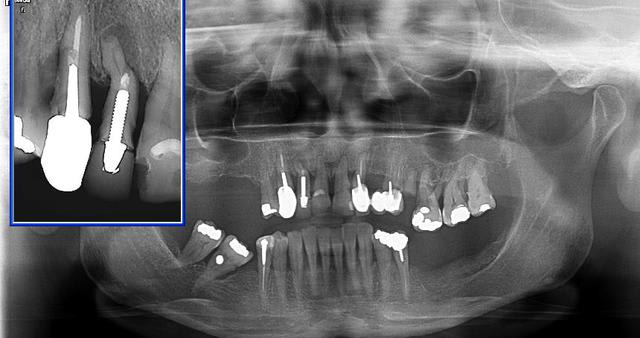

Pj pano haut et bas.

Bon, essayons d’avancer un peu.

Cas drmarcus :

Plan 1

Extraction de toutes les dents

PCA immédiate

Temporisation 3 mois

MCI ou MCD

Plan 2

Extraction partielle

Pour la phase de temporisation, je n’ai pas bien compris quel était la solution provisoire

Plan 3

Empreinte des maxillaires + DVO

Réalisation d’un Positscan

Scanner

S.I.A .O. (simulation assistée par ordinateur)

Utilisateur banni

Avantage du plan 3, le patient conserve son bridge pendant la phase d’étude.